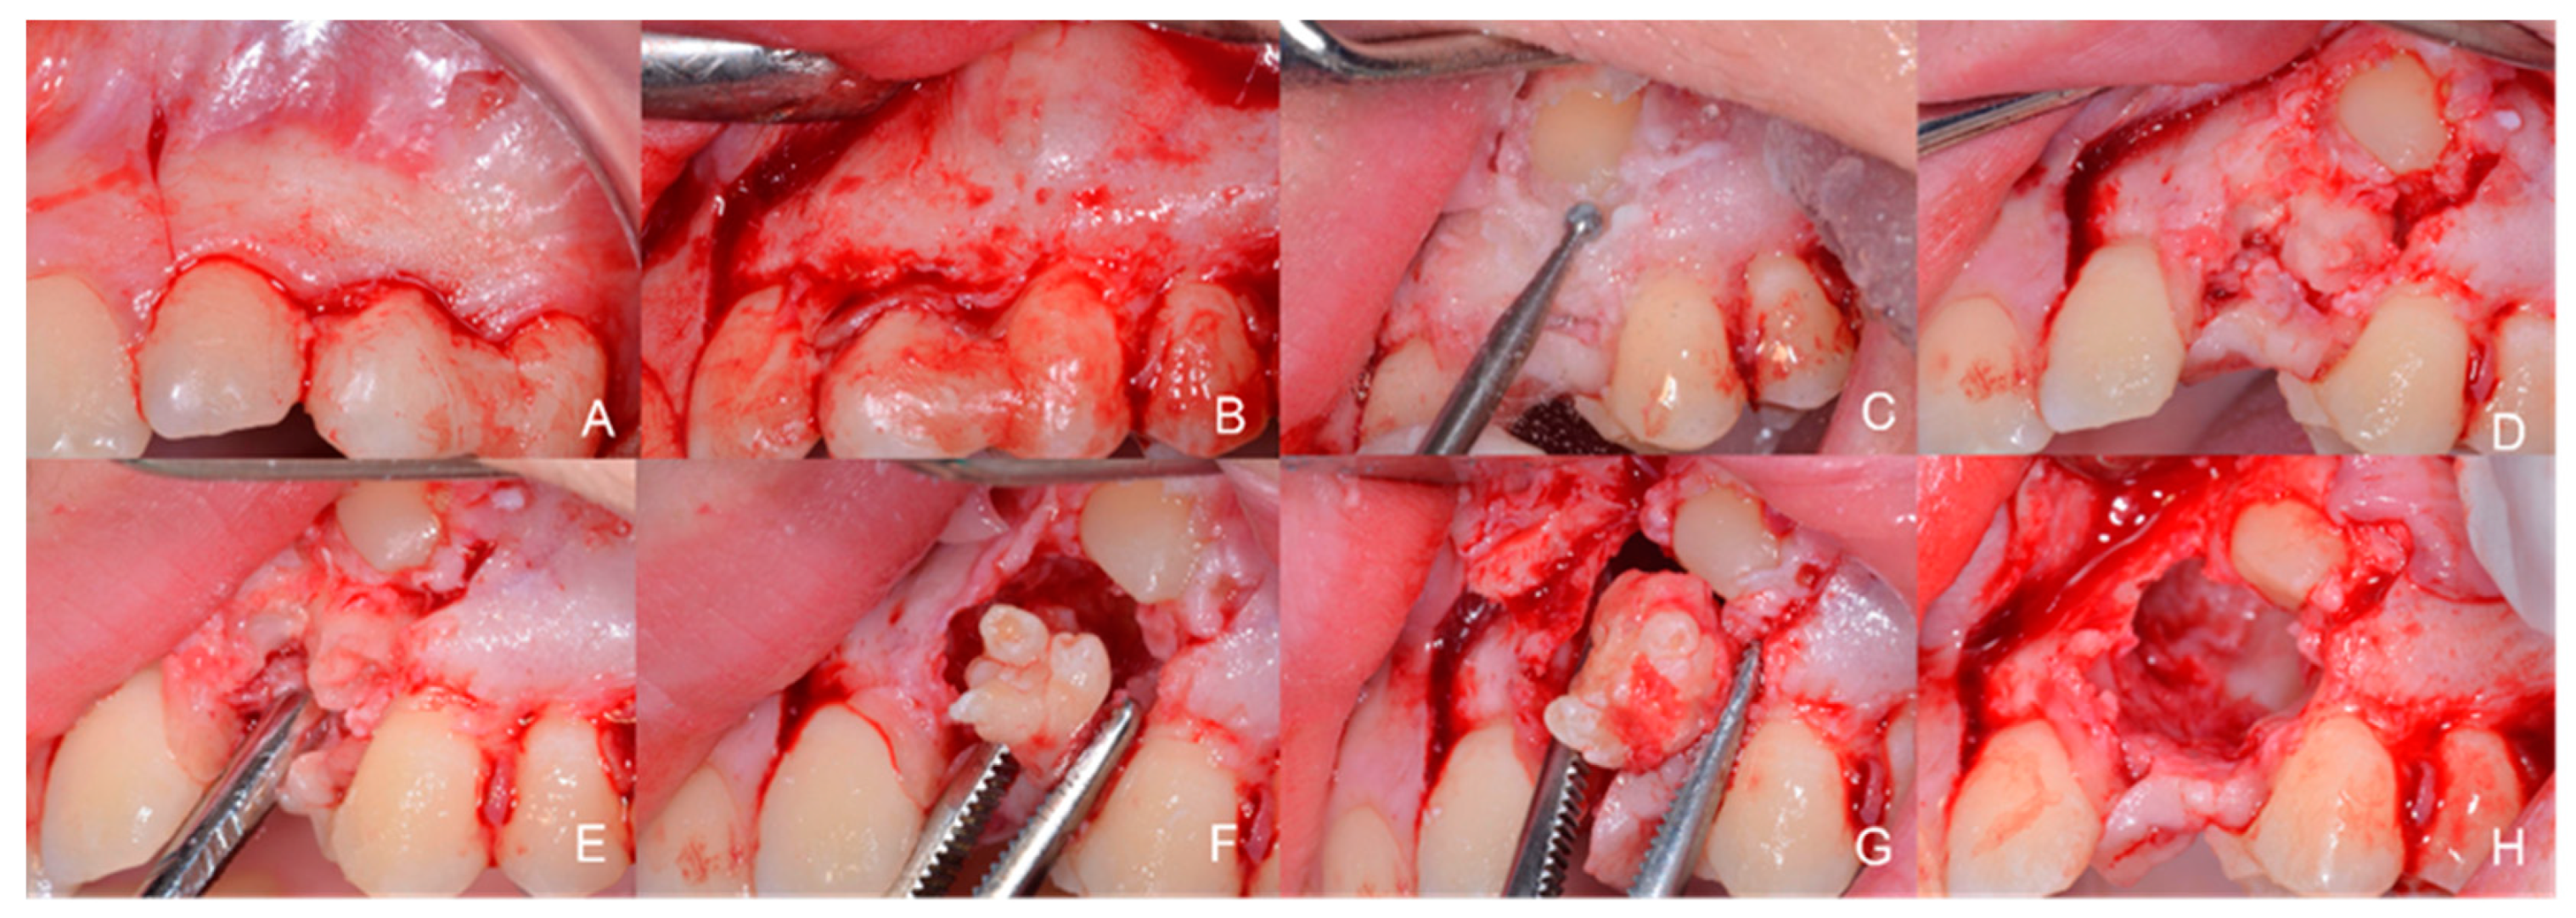

1.2. Case Number 2